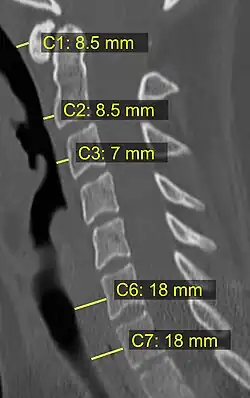

CT scan or X-ray images are evaluated for the presence or absence of directly visible fractures. In addition, indirect signs of injury by the vertebral column are incongruities of the vertebral lines,[11] and/or increased thickness of the prevertebral space:[12]

![CT scan with upper limits of the thickness of the prevertebral space at different levels.[12]](./_assets_/CT_of_prevertebral_space.jpg)